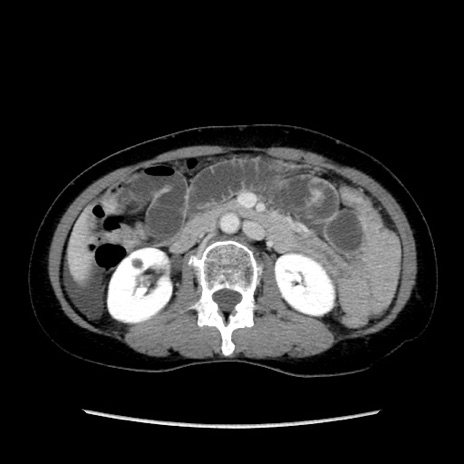

症例32(横断像)

【症例】40歳代 女性

【主訴】上腹部痛、嘔気・嘔吐

【現病歴】約9時間前頃から急に上腹部痛、嘔気、嘔吐が出現。改善しないため救急要請。

【既往歴】子宮頚癌(広汎子宮全摘術、放射線療法)、腸閉塞